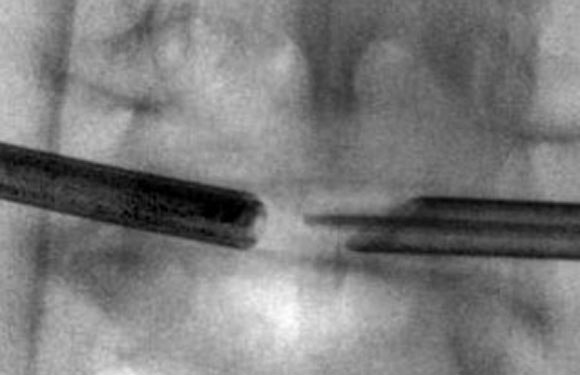

Click to watch a video that shows the back of a cervical disc space with a fragment of herniated disc being removed and the back of a decompressed disc space with the dura pulsating over the spinal cord.